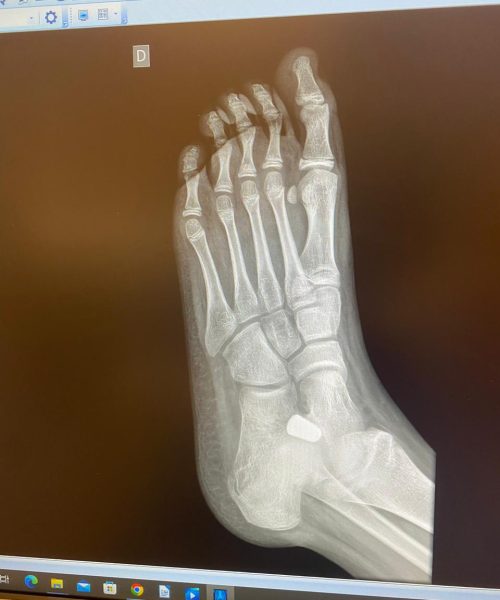

O pé plano é uma condição em que a curvatura normal do arco do pé é reduzida, resultando em uma superfície de apoio mais ampla ao caminhar.

O tratamento para pé plano é indicado para pacientes que experimentam dor, instabilidade ou outros sintomas relacionados ao pé plano. Pode incluir opções não cirúrgicas, como suportes ortopédicos, ou cirúrgicas em casos mais graves.

O tratamento pode envolver medidas conservadoras, como fisioterapia, exercícios e o uso de palmilhas ortopédicas. Em casos mais severos, a cirurgia para reconstrução do arco do pé pode ser considerada.

Os riscos cirúrgicos incluem infecção, reações à anestesia e, em casos raros, a necessidade de revisões cirúrgicas. A avaliação desses riscos deve ser discutida detalhadamente com o cirurgião.

A recuperação pode variar, mas geralmente envolve um período de imobilização seguido por fisioterapia para restaurar a função e a força do pé.